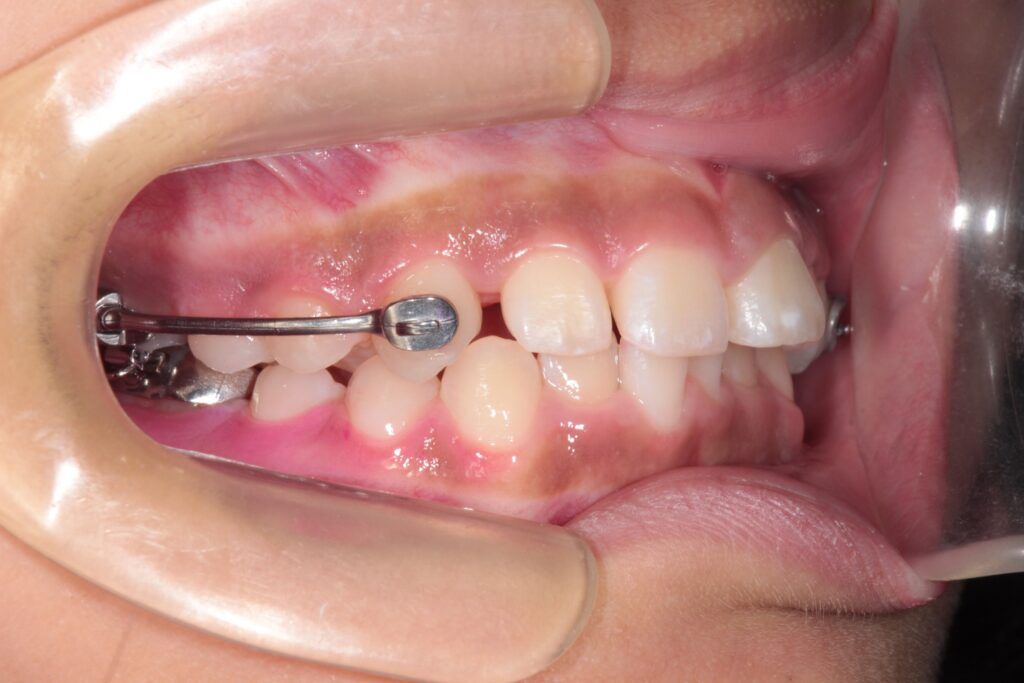

カリエールの役割:奥歯を正しい位置へ

カリエールは、奥歯全体を後方へ移動させることで、理想的な咬み合わせに導く装置です。

頬側に細いバーを取りつけて、ゴムの力で歯を後方に引っ張る仕組みになっています。

この工程の目的は、咬み合わせ全体のバランスを整えることです。

奥歯が正しい位置に下がることで、前歯や犬歯の位置も自然と理想的な位置に動きます。

約3ヶ月間の使用で、臼歯の関係が改善し、次に予定していた本格矯正へと移行できる状態になりました。